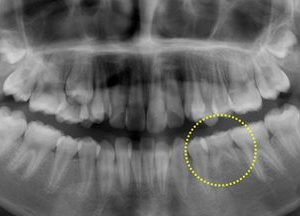

続きを読む10歳の女の子、上下の前歯がガタガタで八重歯が気になるとのことで矯正相談に来られました。レントゲン撮影をしたところ、下あごの第二小臼歯が1本先天欠損しており、第二乳臼歯(黄色に丸囲い)が残存していることがわかりました。 ...